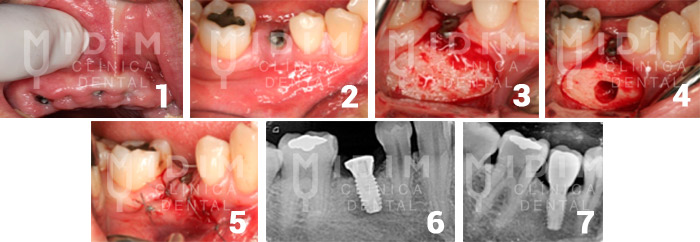

- El diagnóstico se confirma si al presionar con el dedo de este modo el dolor aumenta.

- El paciente al que se le ha colocado este implante vino al cabo de varios días con dolor intenso.

- Se levanta la encía de la zona.

- Se hace una pequeña perforación en el hueso hasta llegar al implante y liberar la presión.

- Se sutura.

- Radiografía del implante tras la cirugía.

- Radiografía al cabo de 1 año donde se ve la curación y el implante ya con el diente colocado.